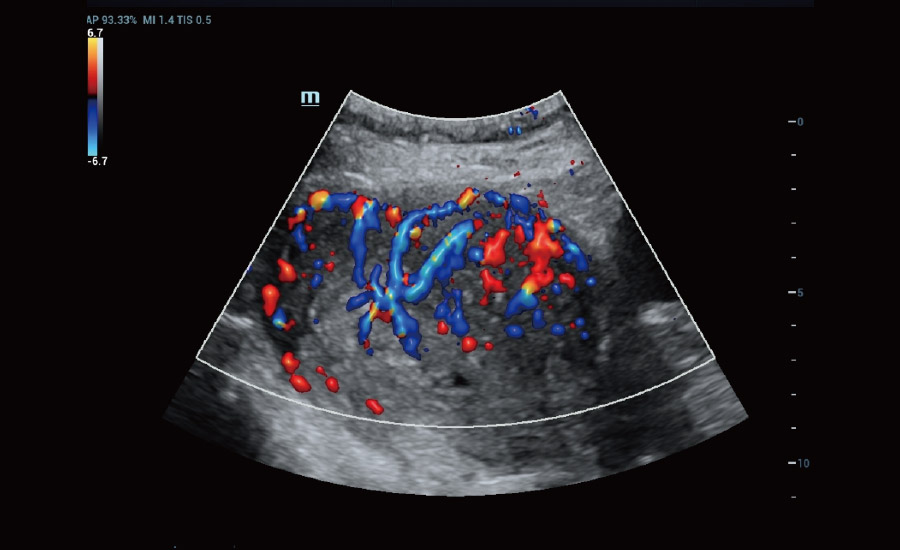

UMA (angiografia ultramicroscĆ³pica)

A tecnologia inovadora elimina as limita??es das tradicionais imagens com Doppler. Com resolu??o espacial e sensibilidade de fluxo ultra-altas, permite a detec??o de perfus?es de fluxos muito sutis e lentos, ampliando assim a aplica??o clĆnica da avalia??o qualitativa e quantitativa do ultrassom no cĆ©rebro fetal, rins, placentas, endomĆ©trios, ovĆ”rios etc.

UMA ā Fluxo uterino e endometrial